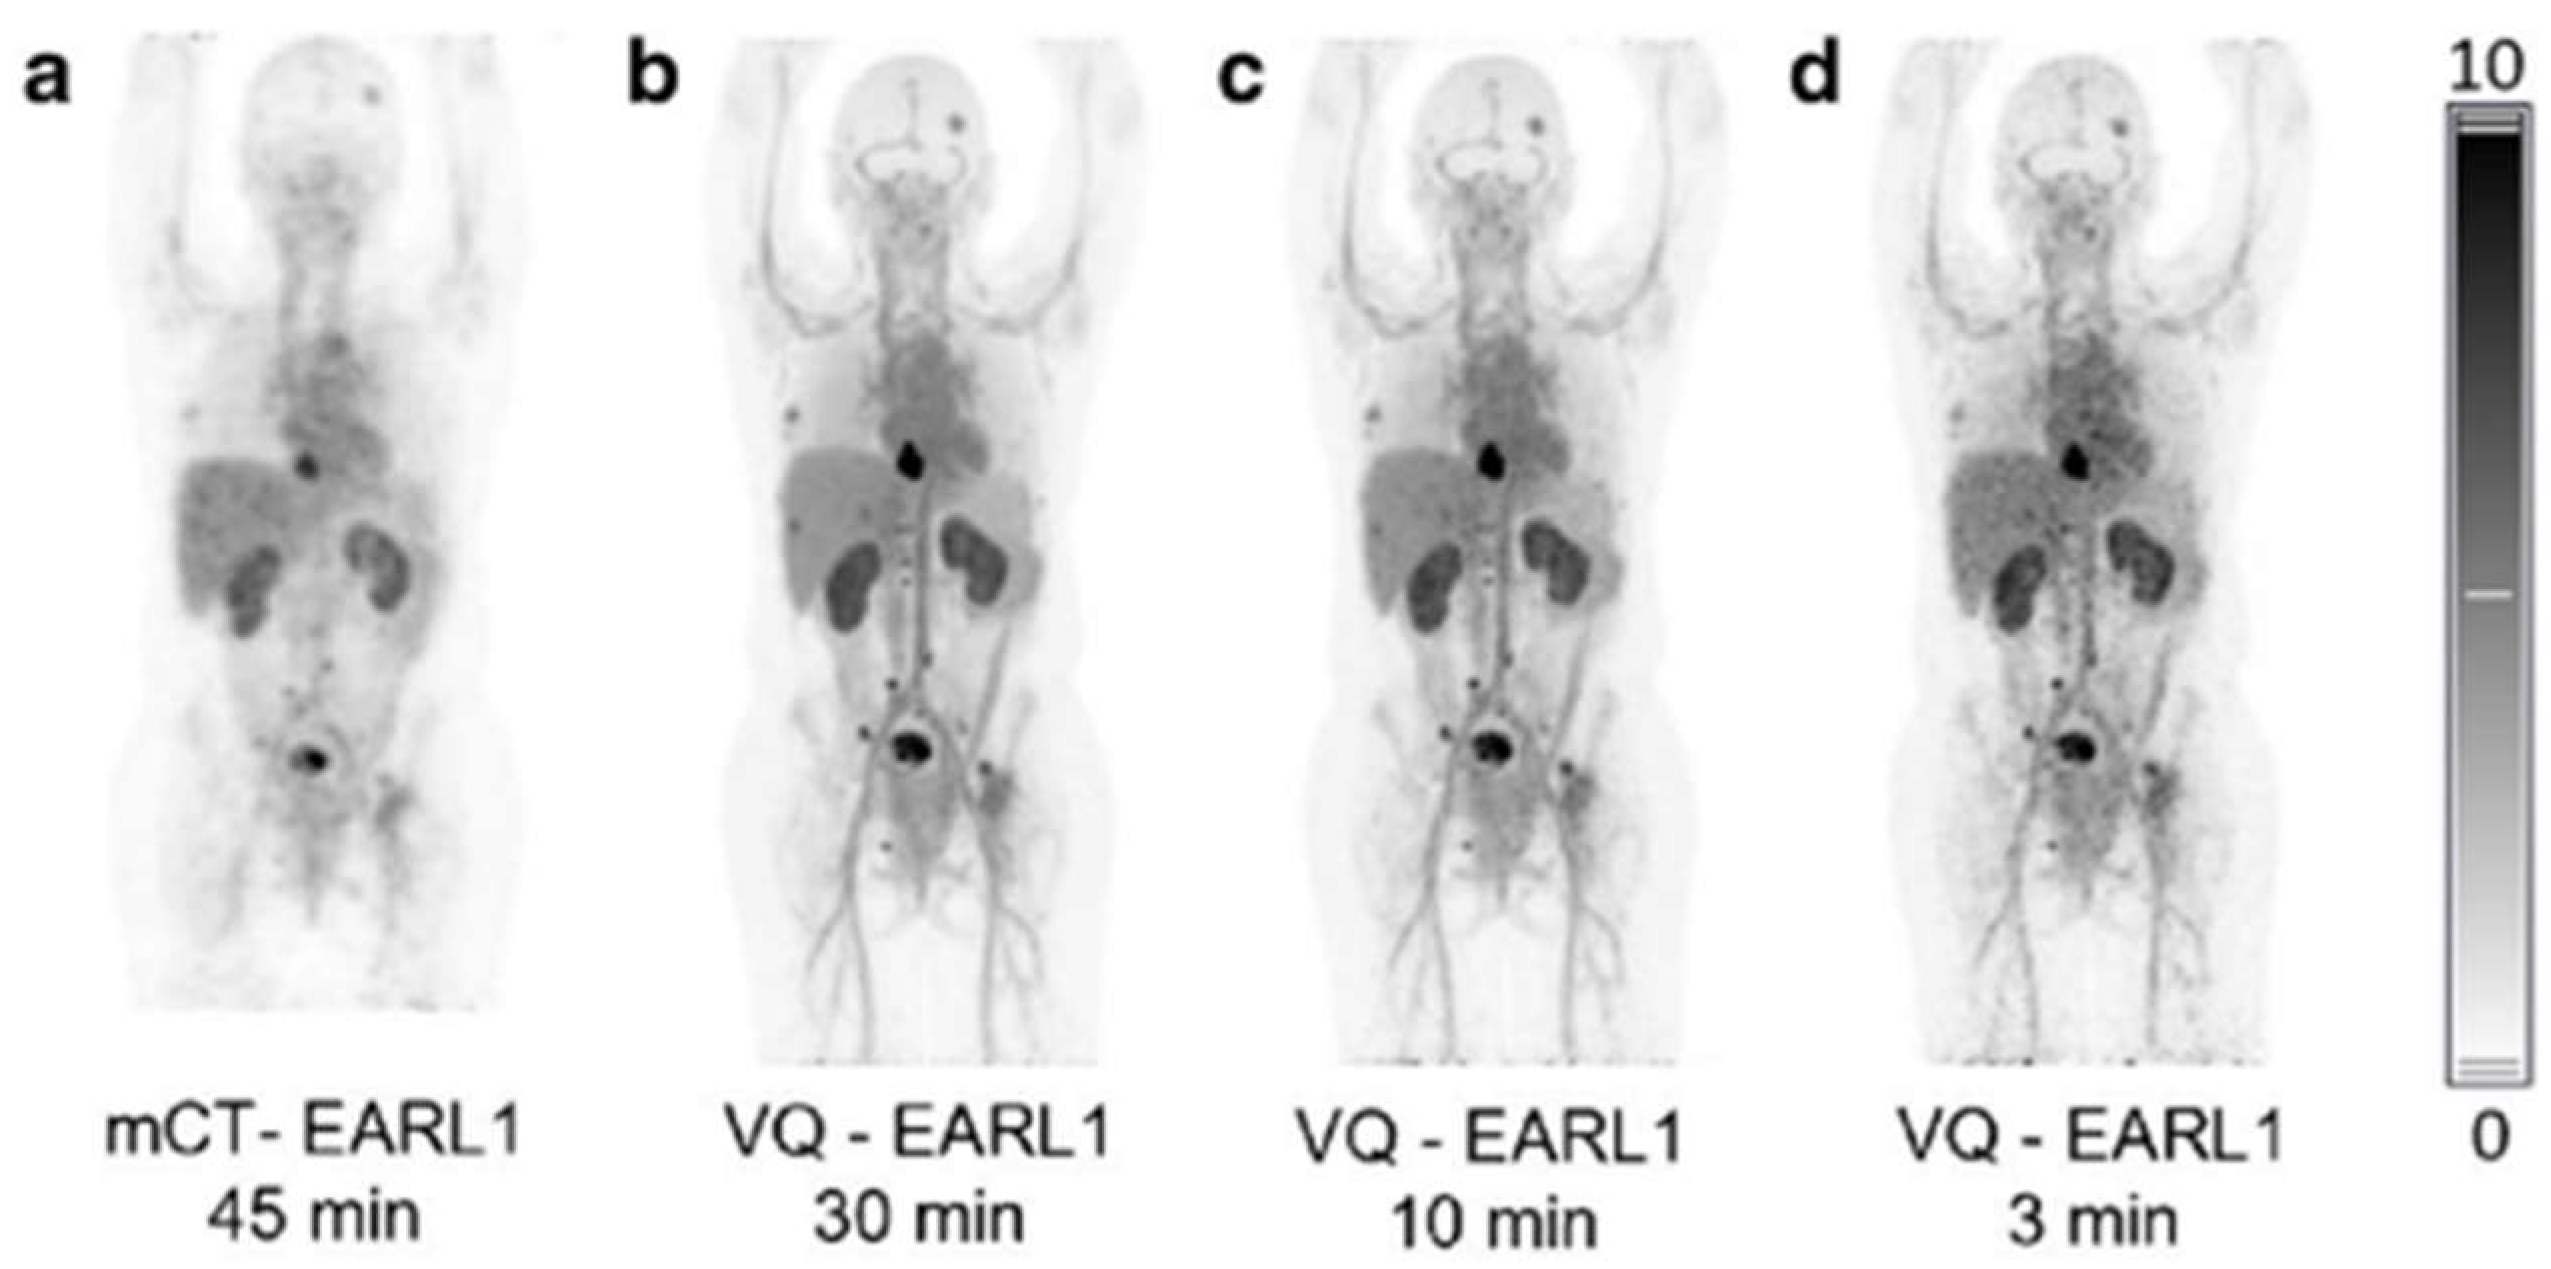

- Mohr, P.; van Sluis, J.; Providencia, L.; van Snick, J.H.; Lub-de Hooge, M.N.; Willemsen, A.T.; Glaudemans, A.; Boellaard, R.; Lammertsma, A.A.; Brouwers, A.H.; et al. Long Versus Short Axial Field of View Immuno-PET/CT: Semiquantitative Evaluation for (89)Zr-Trastuzumab. J. Nucl. Med. 2023, 24, jnumed.123.265621. [Google Scholar] [CrossRef]